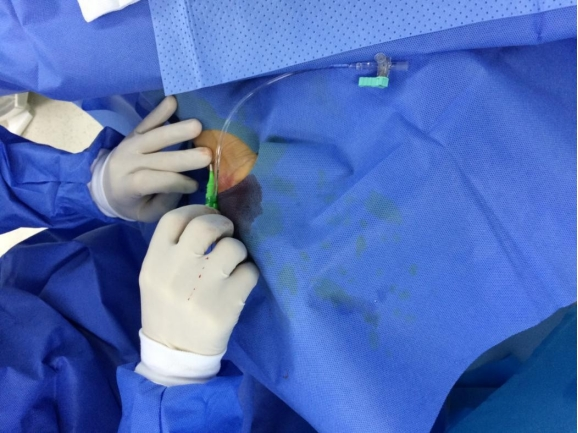

封管:

用装有肝素盐水的注射器接桡动脉鞘管三通管,打开三通阀回抽见血后,鞘内注射混有硝酸甘油约200μg的生理盐水预防血管痉挛,再推入适当肝素盐水,关掉三通阀完成封管。